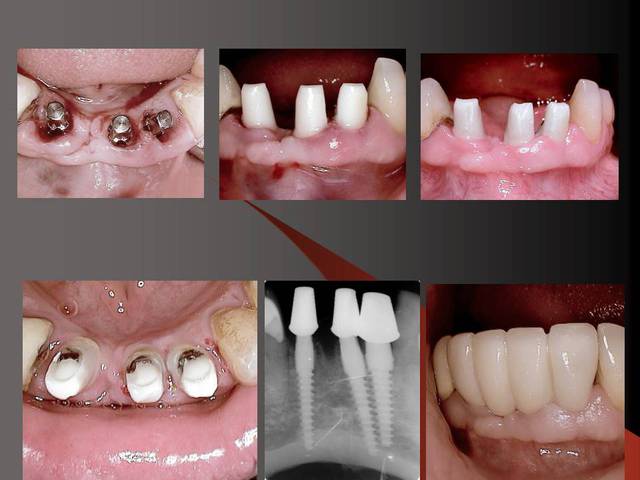

En dessous il y a des photos, dans une on voit (troisième) qu il n y a pas de resorption de l´os après 14 ans, ce que l´on voit c´est l´os très fin condensé sur l´implant.

Photos d'un cas d'extraction implantation immédiate, stabilité primaire (de mémoire) assez élevée.. 60/70 N ..démontage du gingiva clips et du shuttle, pilier serré 40N, couronne procera

Merci pour le cas, bien fait. Belle présentation photo.

Le contour gingival est net, belle guérison, c'est à combien de semaine ?

La pose de la couron nec'est faite 8 semaines apres l'extraction implantation immédiate, la particularité de ce systeme permet de ne pas démonter le shuttle ni la gingivaclip pour l'empreinte..je pense que ca aide bien à la qualité gingivale...radio controle ci jointe